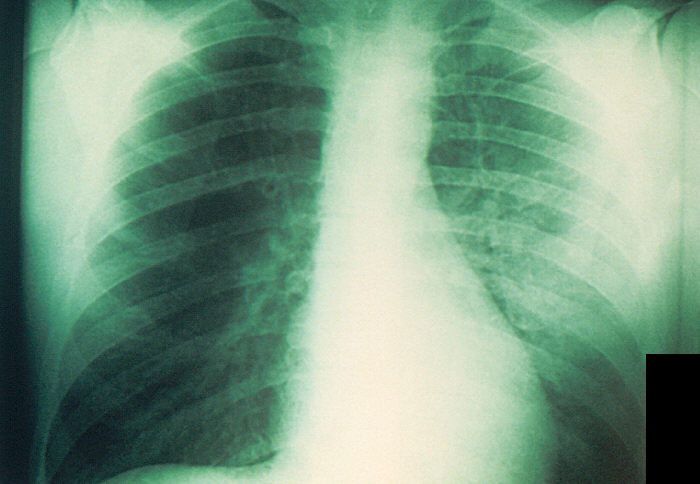

B. bronchiseptica infects a broad range of mammals and gives rise to a wide spectrum of diseases. It is a major cause of “kennel cough” in dogs, which is characterized by persistent, forceful cough, and bronchopneumonia in cats. It is commonly associated with atrophic rhinitis in pigs and snuffles in rabbits. Human disease is rare, but has occurred in individuals that are immunocompromised and occasionally occurs following contact with sick animals. Diseases in this case include pneumonia, sinusitis, and nosocomial tracheobronchitis.

Host symptoms varies depending on the species affected and may include coughing, sneezing, nasal discharge, swelling of the lymph nodes in the neck, lethargy, fever, and difficulty breathing. In severe cases, B. bronchiseptica can be life threatening.